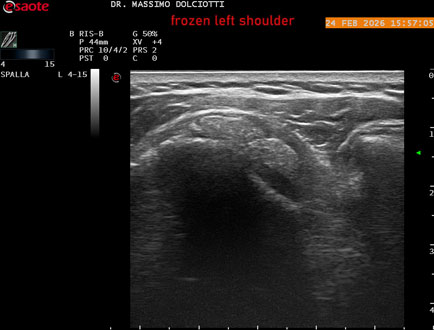

Data inserimento: 02/03/2026

Ecografia del: 24/02/2026

Strumento: Esaote MyLab Eight

Sonda: Lineare Multifrequenza 4-15 MHz

Età Paziente: F 71 anni

Motivazione dell'esame: da 1 mese dolore alla spalla sinistra, anche di notte.

Commento all'esame: le immagini ed il video documentano il tendine sovraspinato sinistro spiccatamente disomogeneo, per presenza di immagine iperecogena, delle dimensioni di 21 x 4 mm, da ricondurre a estesa calcificazione. Quadro clinico di spalla congelata.

Conclusioni: spalla sinistra congelata (frozen left shoulder).

In collaborazione: Dr.ssa Marica Manfredi - Ancona, Dr. Ilir Qose - Ancona

Presentazione: Dr. Massimo Dolciotti - Ancona

Elaborazione digitale: Andrea Dini - Ancona